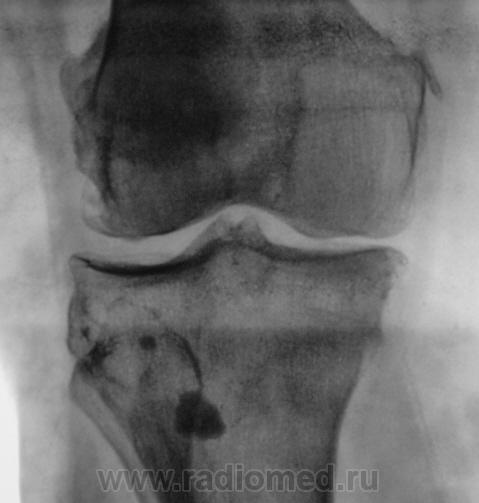

Пациентка направлена в рентгеновский кабинет на рентгенографию коленного сустава в диагнозом - "Артроз".

Валентин Львович, может это быть хондроматозом? И есть гонартроз+медиальный эпикондилит.

Да я не думаю, что это хондроматоз, пока сам в нерешительности, решил послушать мнения коллег.

Гонартроз 2 стадия.Обызвествление параартикулярных мягких тканей .Хондроматоз несколько по-другому выглядит и локализуется более скученно в слизистой сумке.Часто встечала в локтевом и плечевом суставах, в коленном ни разу не видела.

Если это системный процесс (метаб. кальциноз), то то же самое было бы и на снимках локт сустава? Крупное костное тело - сесамовидная кость либо  привет от Осгуд-Шлаттера. Насчет мелких - кроме цистицеркоза ничего в голову не приходит.